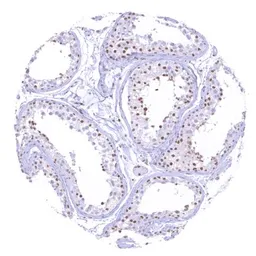

IHC-P analysis of human testis tissue using GTX640917 SMARCA2 antibody [HMV337] HistoMAX™.

A distinct nuclear SMARCA2 staining in all intratubular cells except Sertoli cells.